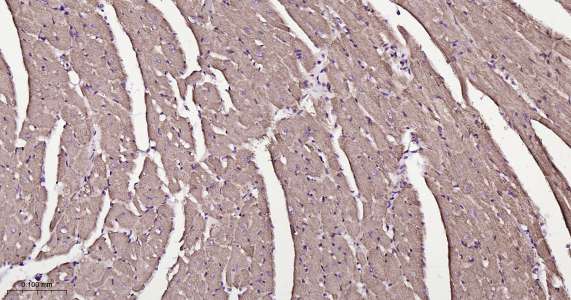

Immunohistochemical analysis of paraffin embedded mouse heart tissue slide using IHC0418M (Mouse ATP5A IHC Kit).